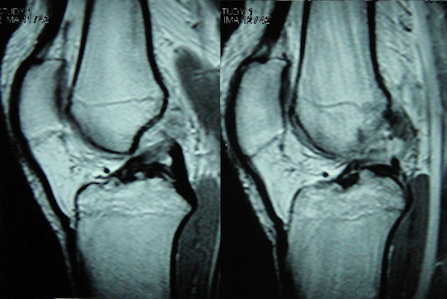

Ciddi diz yaralanması geçiren bütün hastalarda röntgen grafileri elde olunmalı ve kemiklerde kırık olup olmadığı araştırılmalıdır. Ön çapraz bağ yaralanmalarında grafiler genellikle normaldir. Manyetik rezonans görüntüleme ön çapraz bağ yırtıklarının tanısında %90’ın üzerinde doğruluk oranına sahiptir. Ayrıca eşlik eden menisküs, yan bağ ve kıkırdak yaralanmaları ve kemik ödemlerine tanı konabilir. Ancak nadir de olsa MRG yanıltıcı olabilir, bağ işlev görmeyecek derecede yaralanmış olduğu halde MRG’de bağın devamlılığı korunmuş gibi görülebilir. Bu nedenle tedaviye karar verirken MRG tek belirleyici değildir, muayene ve hikaye bulguları da göz önüne alınmalıdır.